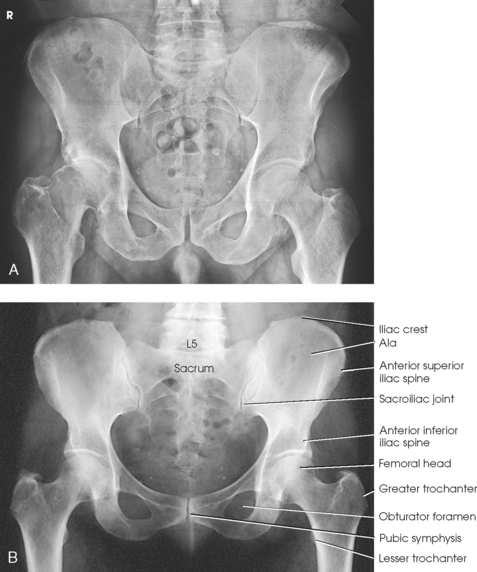

• Center the midsagittal plane of the body to the midline of the grid, and adjust it in a true supine position.

• Unless contraindicated because of trauma or pathologic factors, medially rotate the feet and lower limbs about 15 to 20 degrees to place the femoral necks parallel with the plane of the image receptor (IR) (Figs. 7-15 and 7-16). Medial rotation is easier for the patient to maintain if the knees are supported. The heels should be placed about 8 to 10 inches (20 to 24 cm) apart.

• Check the distance from ASIS to the tabletop on each side to be sure that the pelvis is not rotated.

• Center the IR midway between ASIS and pubic symphysis. In average-sized patients, the center of the IR is about 2 inches (5 cm) inferior to ASIS and 2 inches (5 cm) superior to pubic symphysis (Fig. 7-17).

Structures shown: The image shows an AP projection of the pelvis and of the head, neck, trochanters, and proximal one third or one fourth of the shaft of the femora (Fig. 7-18).